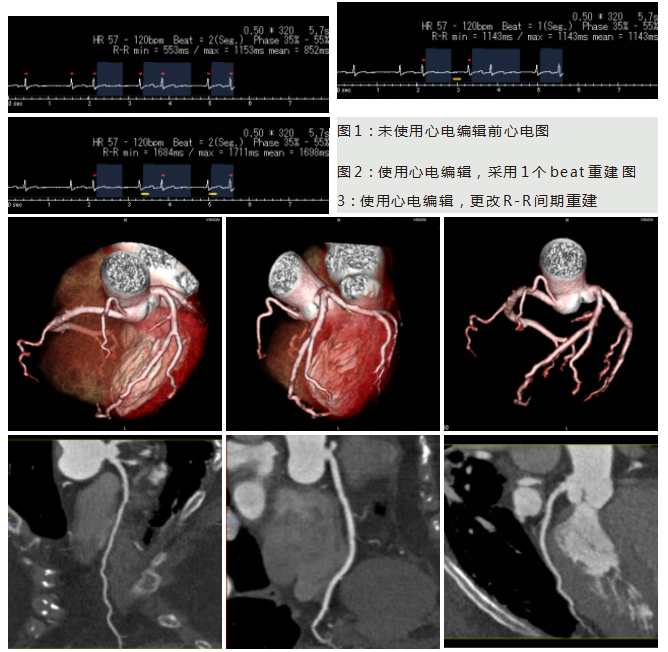

病例一 女, 78 歲,心前區(qū)輕度疼痛, 胸悶氣短, 行冠脈CTA檢查HR 57 - 120 bpm。

病例二 男,30歲, 右心房占位性病變,心功能Ⅱ級(jí),心律失常,心房纖顫, 平均心室率92次/分。

術(shù)前CT檢查:

右心房增大,其內(nèi)可見(jiàn)占位性病變,通過(guò)獨(dú)有的三維染色后處理,可以對(duì)腫瘤進(jìn)行染色, 以便于確定腫塊與心臟血管及其他周圍結(jié)構(gòu)的關(guān)系。

心臟彩超及食道超聲可見(jiàn)右房?jī)?nèi)囊性占位病變;室間隔及左室壁厚度正常高限;雙房大; 左室收縮功能正常; 彩色血流示: 各瓣膜未見(jiàn)病理性返流。

腫瘤病理結(jié)果與CT檢查顯示的大小、 形態(tài)相符合。

術(shù)后CT檢查:

術(shù)后可見(jiàn)右房形態(tài)正常, 心臟其余各結(jié)構(gòu)未見(jiàn)明顯異常。

640層寬體探測(cè)器CT實(shí)現(xiàn)了3 20排譜黃金寬體探測(cè)器1 6 cm的 超寬覆蓋范圍, 與2 7 ms超 快時(shí) 間 分 辨 率 的 完 美 結(jié) 合 , 可 以 實(shí) 現(xiàn) 微 劑 量 高 清 全 景 電 影 成 像 。 特 別 是 在 冠 脈 檢 查 上 , 可 以 實(shí) 現(xiàn)一次心跳下的心臟冠脈檢查, 實(shí)現(xiàn)復(fù)雜心率情況下高清冠脈成像的100 % 檢查成功率。

此外,強(qiáng)大的后處理功能,能提取心臟冠脈,明確腫瘤大小、形態(tài)、表面特征、位置及三維展示與周圍結(jié)構(gòu)的關(guān)系,還能提供心功能等各項(xiàng)參數(shù),以便臨床對(duì)心臟情況做一個(gè)充分的評(píng)估,術(shù)前充分設(shè)計(jì)好方案尤為重要。